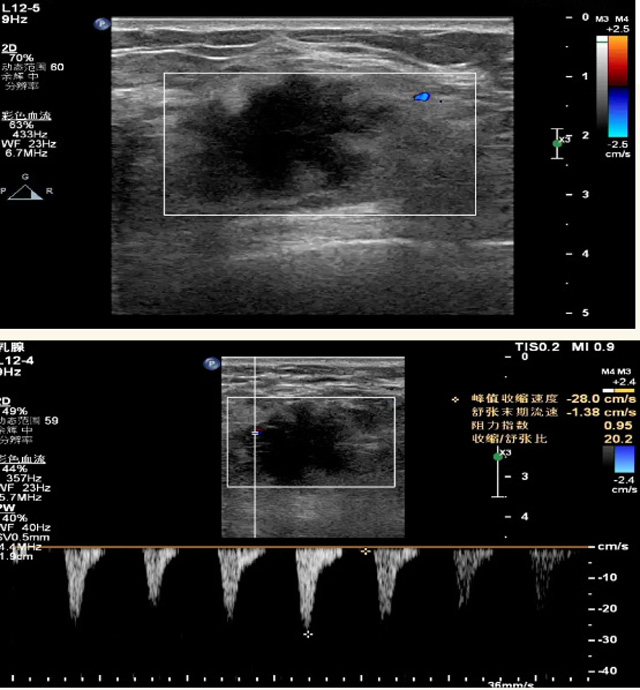

乳腺B超檢查無輻射,對(duì)囊性病變敏感,可以實(shí)時(shí)觀察病灶。超聲引導(dǎo)活檢跟手術(shù)前的定位。就是它對(duì)于微小的鈣化查出率比鉬靶稍微差點(diǎn)。磁共振MRI檢查也是是沒有輻射的,對(duì)備孕跟已經(jīng)懷孕的人士比較友好。不用擔(dān)心這個(gè)輻射影響胎兒?jiǎn)栴}。對(duì)乳腺病灶敏感性較高,致密乳腺病灶、乳腺癌的復(fù)發(fā),準(zhǔn)確鑒別囊性及實(shí)性病變??梢詭椭R床醫(yī)生判斷惡性、良性病變。但是MRI磁共振對(duì)微小鈣化不明顯,微鈣化還是鉬靶靠譜點(diǎn)。檢查時(shí)間比較長(zhǎng),有偽影的影響。費(fèi)用相對(duì)B超,鉬靶高很多。

乳腺B超

磁共振MRI